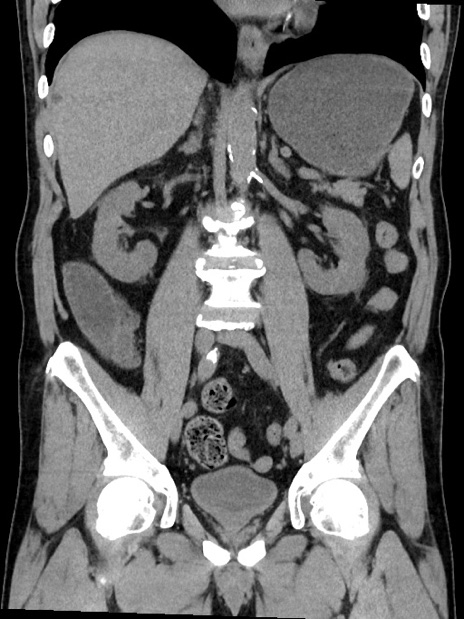

症例35(冠状断像)

【症例】70歳代 男性

【主訴】腹部膨満、嘔吐

【現病歴】昨日より腹部膨満感出現。本日増悪し、仙痛出現。嘔吐あり、受診。

【既往歴】糖尿病、胆摘後

【身体所見】BP 149/80mmHg、HR 74/min、BT 35.9℃、腹部:膨満、軟、圧痛なし。腸雑音減弱あり。上腹部正中切開瘢痕あり。

【データ】WBC 13500、CRP 1.72